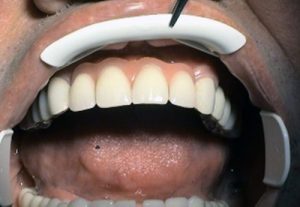

– positive aesthetic effect on facial expression,

charming

and new smile provides better quality of life and restoration of

self-confidence not only

in private life, but also on social and professional level